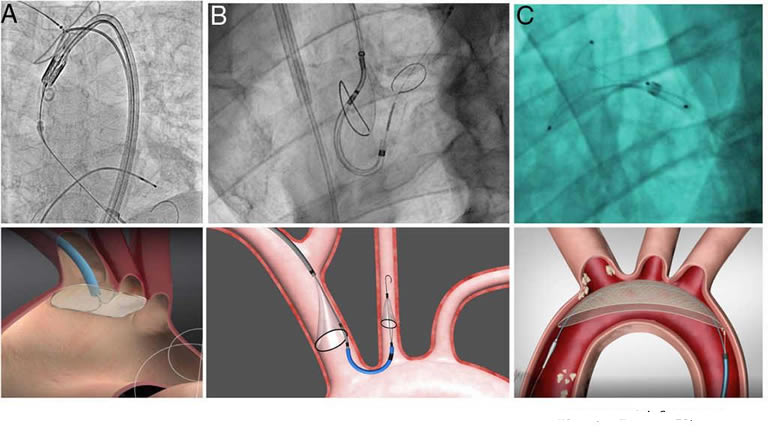

This is a minimally invasive procedure, a new heart valve is inserted without removing the old damaged valve. The new valve is placed inside the damaged valve. Valve replacement is traditionally done through open heart surgery, where the chest is surgically opened for the procedure. The difference with TAVI is that it is performed through very small openings in the arm or groin, so it is not necessary to cut any bones in the chest.